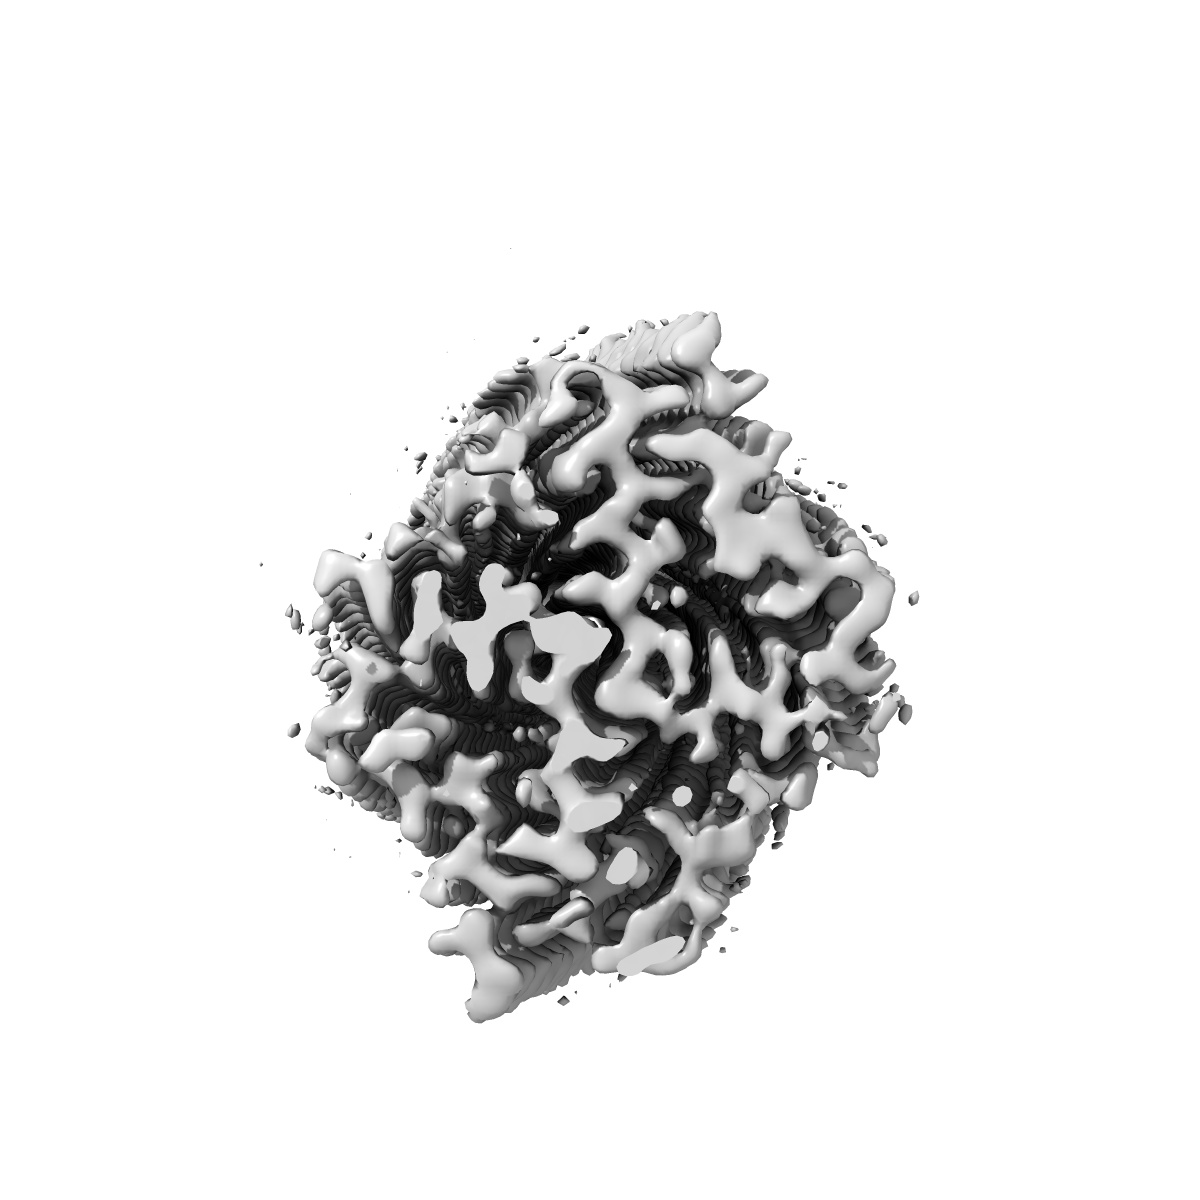

Tropomyosin-receptor kinase fused gene protein (TRK-fused gene protein; TFG) Low Complexity Domain (residues 237-327) P285L mutant, amyloid fiber

Helical reconstruction2.59 Å

Sample: amyloid fibril of protein TFG P285L

Fibril structures of TFG protein mutants validate the identification of TFG as a disease-related amyloid protein by the IMPAcT method.